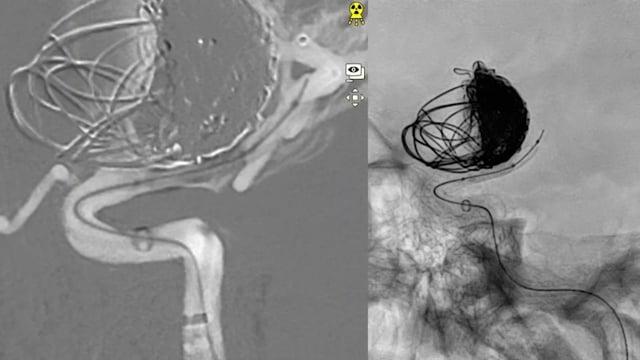

Dive into a curated collection of compelling clinical cases shared by leading experts from LINNC Paris, LINNC Seminars, and LINNC online. Discover a diverse array of complex cases, including aneurysm embolization, AVM/fistula management, stroke interventions, and cSDH treatment. Each case study provides an in-depth exploration of advanced procedures, innovative techniques, and their real-world applications in diagnosing and managing neurovascular conditions.

EVT For Ruptured PICA Aneurysm

AneurysmsStent assisted coiling